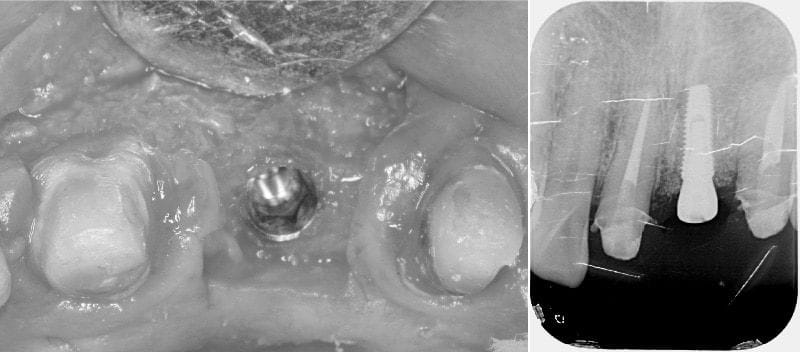

第二階段植牙手術,我們同時應用牙冠增長術,調整兩顆鄰牙的牙肉和齒槽骨高度,讓每顆牙齒在未來的最終假牙的長度、寬度比例能夠符合黃金比例(1.618:1)。植牙的位置與深度角度是最重要的,放在最好的位置才能使未來的每顆牙齒的相對關係能夠和諧美觀、長久耐用。整個療程也很順利在舒眠鎮靜下的狀態完成。

植牙手術置入人工牙根,右為置入人工牙根後拍攝的X光片,確認人工牙根位置符合治療計畫